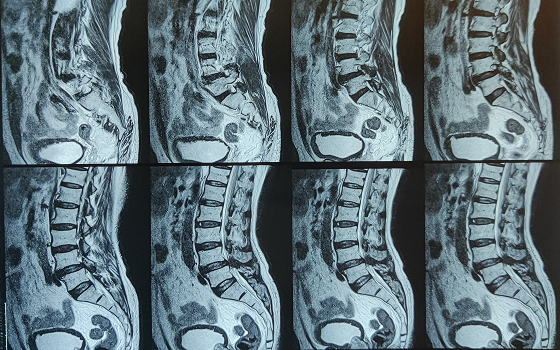

Dr. Somashekar D is an experienced spine surgeon in Bangalore. He is currently practising as a Consultant - Spine Surgery at Manipal Hospital Jayanagar, Bangalore. With nearly 10+ years of expertise in spine care, Dr. Somashekar has established himself as a highly skilled spine surgeon, contributing to over 1,500+ spine surgeries independently, ranging from simple decompressions to complex spinal reconstructions. His practice is deeply rooted in precision-based techniques and evidence-guided clinical protocols, ensuring both safety and long-term functional outcomes for his patients. He is a top spine surgeon in Jayanagar.

• Disc problems

• Degenerative spine disease

Covers a wide range of spine surgeries, including complex spine surgeries.